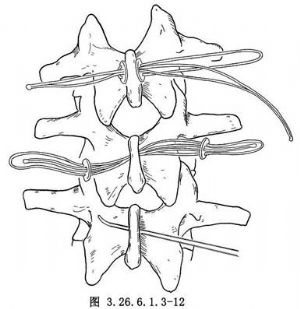

脊柱節段性器械是1973年Luque首先創用的,其特點是在脊柱矯形區內的多個椎體節段上,用鋼絲通過椎板下或棘突基底部將矯形棒固定於椎體上進行脊柱矯形。Luque棒和記憶合金棒均屬於脊柱節段性器械。手術相關解剖見下圖(圖3.26.6.1.3-1~3.26.6.1.3-3)。

9.4 4.椎板下穿鋼絲

取30cm長的醫用鋼絲(直徑1mm),將其對摺,形成雙股,將摺疊鈍端彎成半徑3cm的半圓弧狀。將鈍端插入黃韌帶窗內用雙手使鋼絲貼緊椎板下面通過椎板,鋼絲鈍端由上節椎板的黃韌帶窗露出後,用針持夾夾緊鋼絲鈍端,並提起保持鋼絲張力,將鋼絲由椎板下抽出至椎板上,上下端的鋼絲長度相等爲止,將上下兩段鋼絲交叉於椎板上,以防止鋼絲向椎管內移動壓迫硬膜(圖3.26.6.1.3-11)。

椎板下穿鋼絲的順序,由腰椎開始,依次向近端椎板進行,較爲方便。上胸椎椎板下穿鋼絲比較困難,必須仔細耐心操作。上胸椎部位的鋼絲受張力較大,術後易於折斷。

9.5 5.棘突基底部穿鋼絲法

這是另一種鋼絲固定法。由於操作方便,又不易損傷脊髓。但棘突不牢固,僅適用於青年病人的腰椎棘突部位,少年病人或胸椎由於棘突易於骨折應慎重應用。用棘突打孔鉗在棘突基底部打孔,兩側同時將對摺雙股鋼絲通過三孔墊片的骨孔穿出,拉緊鋼絲後將預彎的合金棒置入鋼絲間,將鋼絲旋緊固定即可(圖3.26.6.1.3-12)。